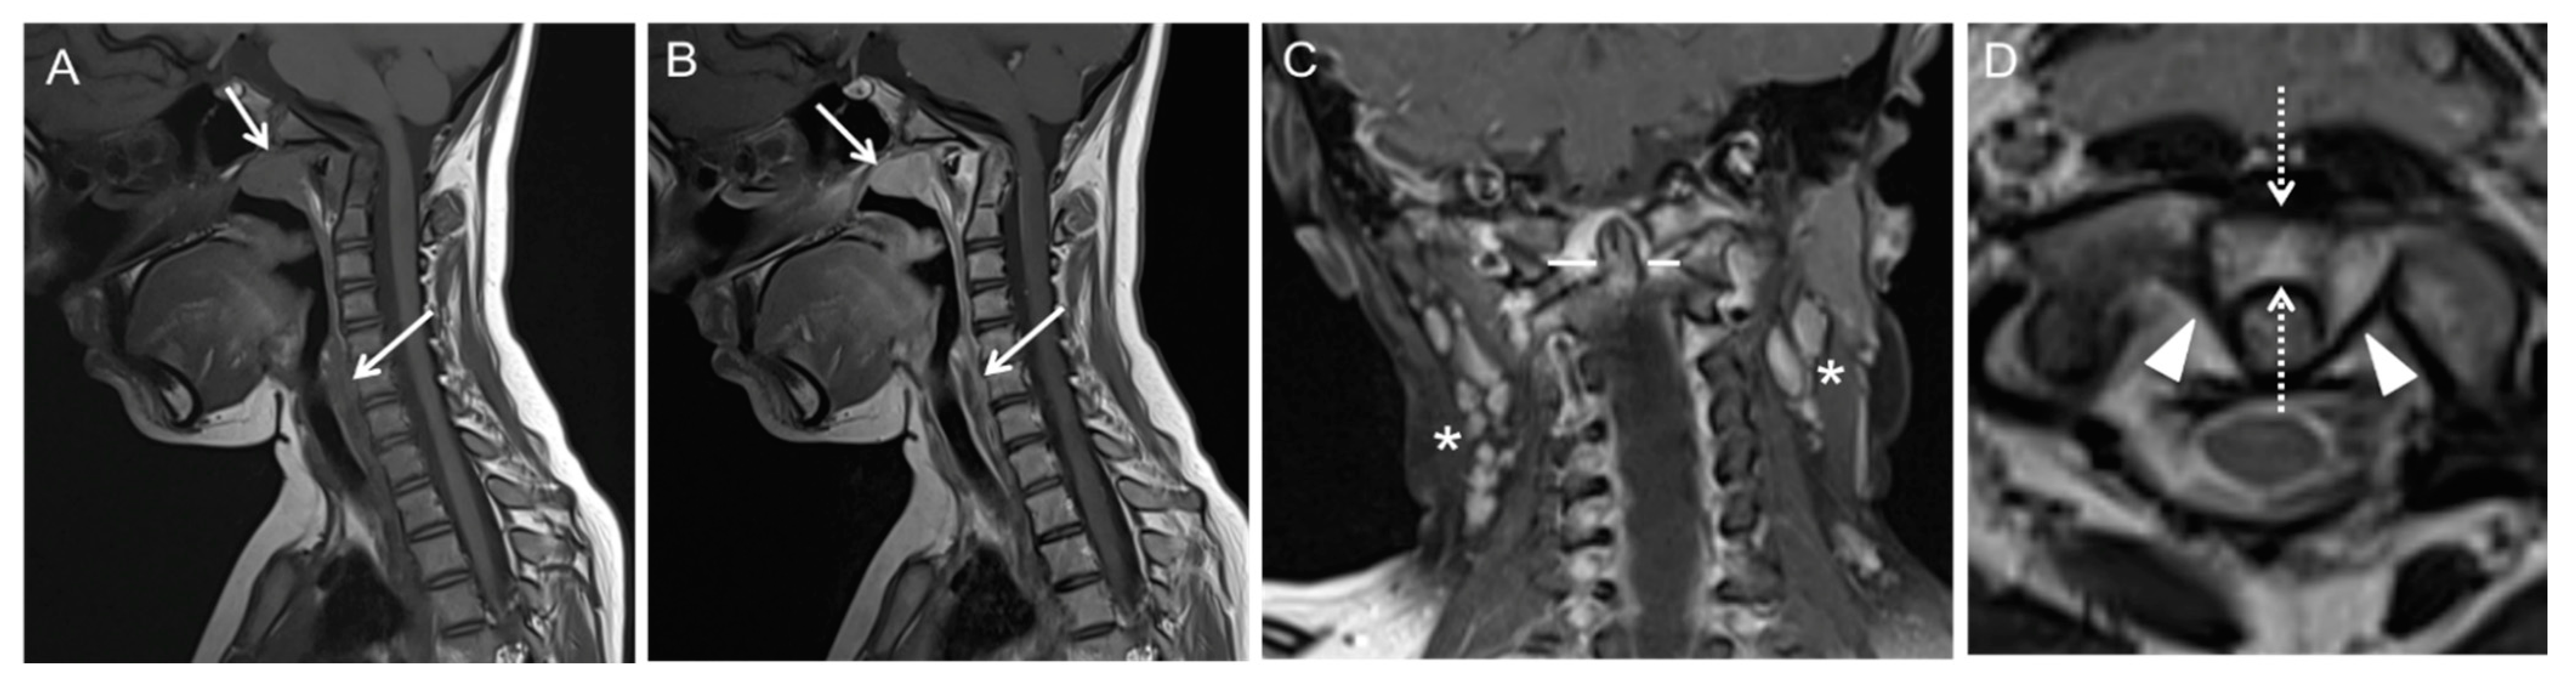

Illustration of Three Pediatric Cases of MRI in Inflammatory Nontraumatic Atlantoaxial Rotatory Subluxation